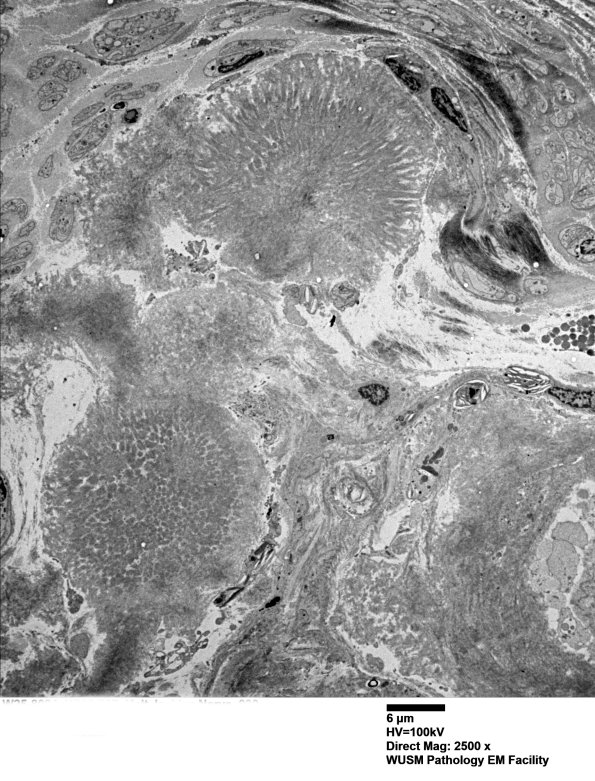

Washington University Experience | PERIPHERAL NEUROPATHY | 14 AMYLOID NEUROPATHY | 1F7 (Case 1) Nerve_030 - Copy

1F7,8 Several subperineurial/endoneurial cores of amyloid composed of fingers of fibrillary processes. (electron micrographs)